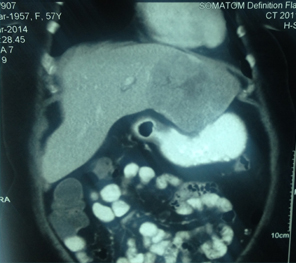

HCC in a non cirrhotic liver

Large HCC in seg 2 & 3

Large HCC in seg 2&3